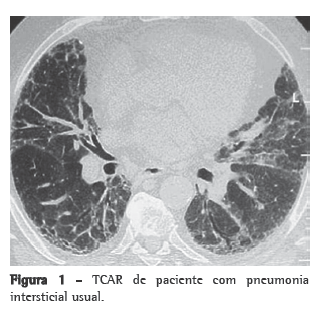

Para a maioria dos cirurgiões torácicos, tanto o lobo médio como os segmentos lingulares são anatomicamente locais de fácil ressecção, tanto por minitoracotomia, quanto por videotoracoscopia. Nos demais segmentos pulmonares, a retirada de amostras envolvendo regiões centrais e periféricas é dificultada pela necessidade de se realizar uma cunha no parênquima com um tamanho adequado. Para obter esse padrão de amostra, a cunha deve estender-se além dos 2 cm de profundidade, a espessura média da região periférica pulmonar (Figura 2).

A retirada do tecido pulmonar do lobo médio e do segmento lingular permite a obtenção de amostras com volumes satisfatórios, bastando muitas vezes apenas um disparo de grampeador endoscópico ou uma linha de sutura.